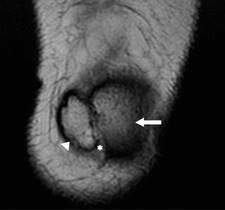

Se trata de paciente femenino de 43 años de edad, que acudió al Departamento de Resonancia Magnética por dolor en la cara anterior de la rodilla izquierda, se le realizó resonancia magnética, en la que se encontró como variante anatómica duplicación patelar (Figura 1).

Figura 1: Resonancia magnética de rodilla izquierda en secuencia T2 coronal, donde se observa patela accesoria (cabeza de flecha) y patela (flecha), así como tejidos blandos en medio de ambas estructuras (*).